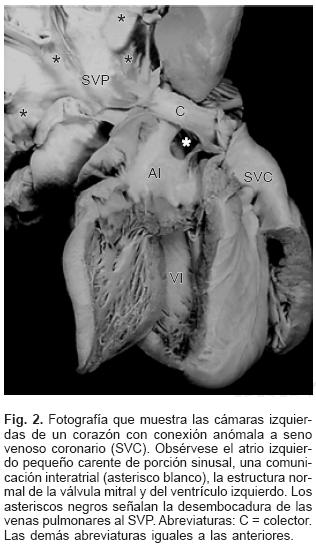

En todos los especímenes el SVP estuvo independiente, separado del atrio izquierdo y ubicado por detrás y un poco por encima de esta cámara cardíaca incompleta y pequeña (Figs. 1 y 2). El SVP se continuó con un vaso colector que siguió diferentes trayectos según el sitio de conexión anómala; en el tipo a vena cava superior el colector ascendió por detrás del bronquio derecho o del izquierdo según la posición de esa vena; en dos especímenes la obstrucción del colector fue intrínseca por estrechez del mismo en el sitio de su desembocadura (Figs. 3A y 4) y en un espécimen el colector siguió un trayecto anómalo entre la rama derecha de la arteria pulmonar y el bronquio derecho lo que provocó obstrucción extrínseca en el mismo (Fig. 3B). En el sitio de conexión anómala a la vena vertical el SVP recibió las venas de ambos pulmones y a través de un colector corto se continuó con la vena vertical ubicada del lado izquierdo, ésta a su vez lo hizo con el tronco venoso braquiocefálico izquierdo que desembocó en la vena cava superior y ésta en el atrio derecho (Fig. 5); en un espécimen existió obstrucción intrínseca en la vena vertical (Fig. 6).

En la CATVP al atrio derecho el SVP se integra en la parte posterosuperior de esta cámara a través de un colector muy corto (Fig. 7). En el sitio de conexión al seno venoso coronario el colector venoso desembocó en el extremo izquierdo de dicho seno el cual estuvo dilatado (Figs. 2 y 8). El orificio de desembocadura del seno venoso coronario en el atrio derecho fue muy amplio y se situó por debajo de la comunicación interatrial (Fig. 9). En un espécimen existió estrechez intrínseca del colector en el sitio en que se unió al seno venoso coronario. En la conexión anómala infradiafragmática el SVP recibió las venas de ambos pulmones y se continuó con un colector largo que acompañó al esófago, atravesó el hiato esofágico y descendió hasta desembocar en la vena porta justo antes de penetrar al hígado (Fig. 10). Todos los corazones de este grupo presentaron obstrucción extrínseca a nivel del hiato esofágico y en dos especímenes se agregó obstrucción intrínseca en el colector antes de su desembocadura en la vena porta (Fig. 10).

En el grupo mixto el trayecto de los colectores provenientes de cada pulmón dependió de los sitios de conexión anómala (Tabla II). Los setenta y tres corazones en situs solitus e inversas presentaron un defecto septal interatrial de tipo orificio oval (Figs. 2, 4, 7 y 9), mientras que en los treinta corazones con dextroisomerismo existió un atrio común y una bandeleta septal interatrial que separó dos grandes comunicaciones (Fig. 11). Todos los corazones presentaron dilatación de las cámaras derechas, del tronco y ramas de la arteria pulmonar así como hipertrofia del ventrículo derecho (Fig. 12). Respecto a las cámaras izquierdas el atrio fue pequeño e incompleto por carecer del SVP (Fig. 2), el ventrículo izquierdo y la válvula mitral tuvieron características normales. Las cardiopatías asociadas en los setenta y seis corazones con situs solitus e inversus se consignan en la Tabla III. Los treinta corazones con dextroisomerismo presentaron un patrón complejo de asociación de anomalías intracardíacas y vasculares (Tabla IV); en las Tablas V y VI se muestran respectivamente los tipos de conexión atrioventricular y ventriculoarterial en dextroisomerismo.